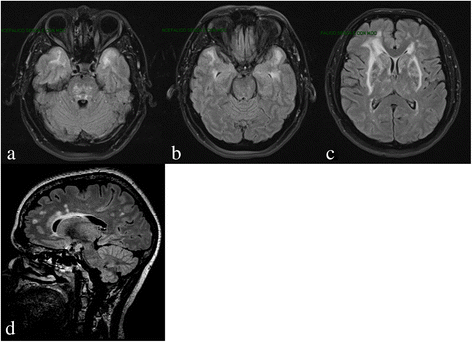

Cerebral autosomal dominant arteriopathy with subcortical infarcts and leukoencephalopathy (CADASIL) is the most common and best known monogenic small vessel disease. Here, we review the clinical, neuroimaging, neuropathological, genetic, and therapeutic aspects based on the most relevant articles published between 1994 and 2016 and on the personal experience of the authors, all directly involved in CADASIL research and care. We conclude with some suggestions that may help in the clinical practice and management of these patients.